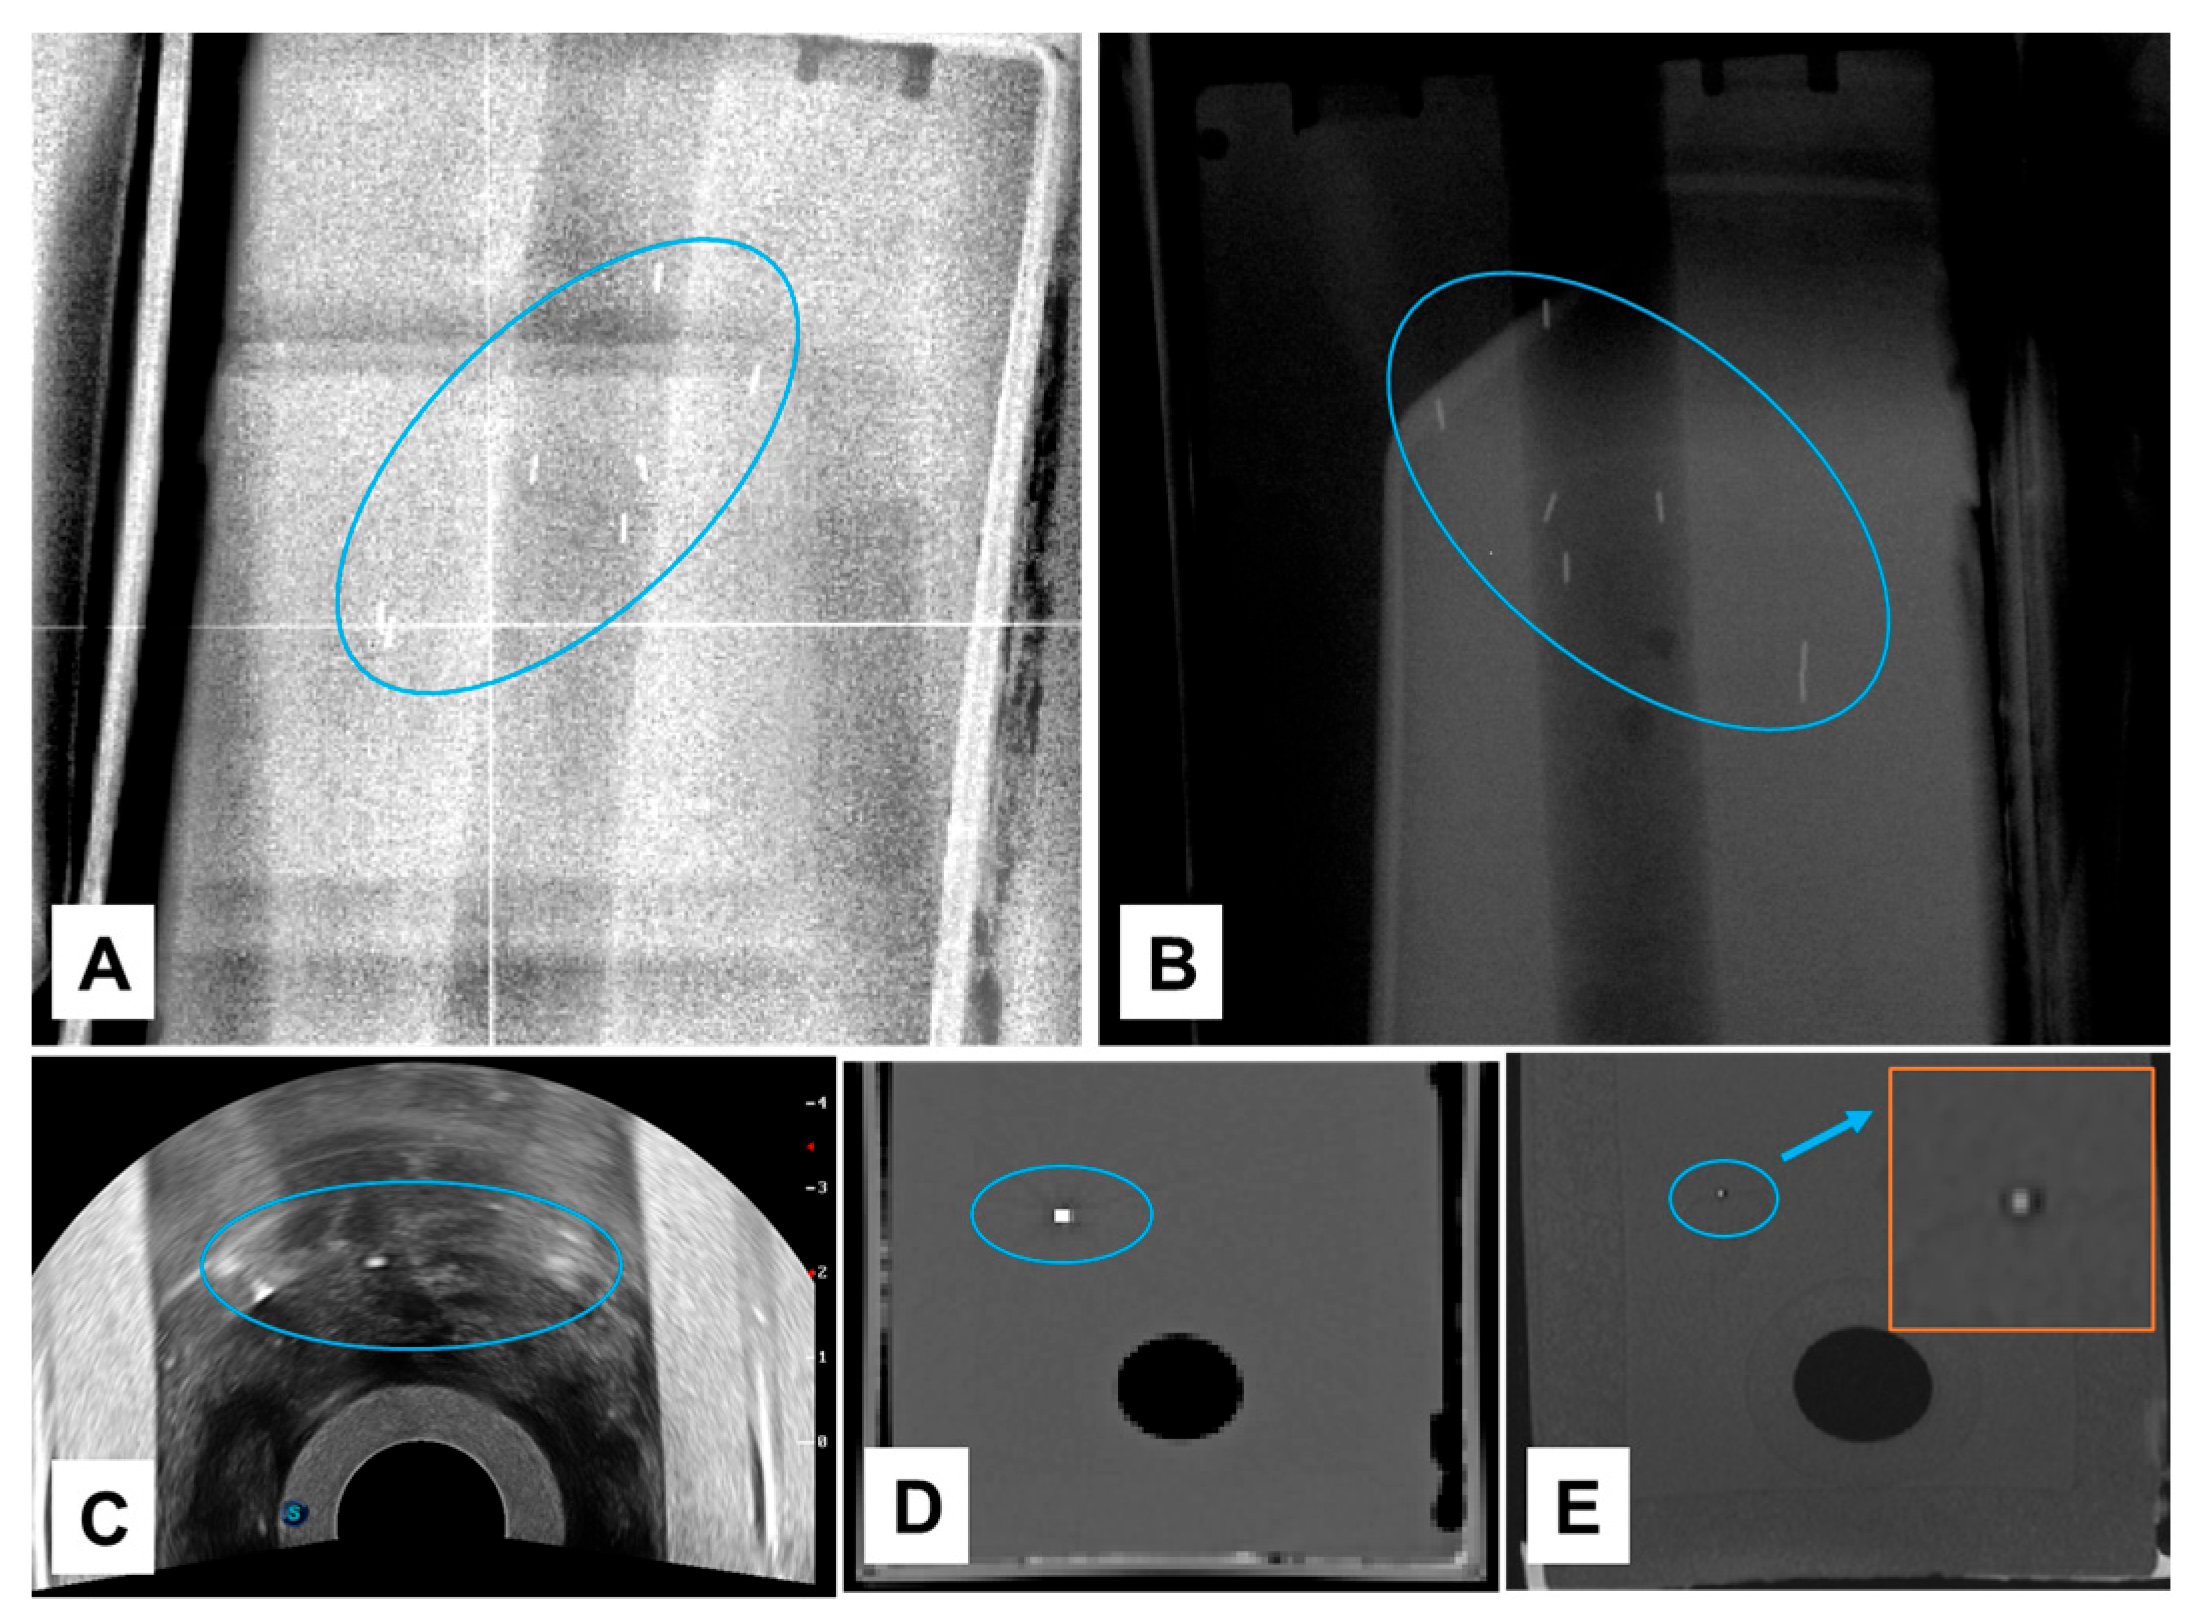

3.1. NOVA Marker Visibility in Phantom

3.2. NOVA Marker Artifacts on CT Images